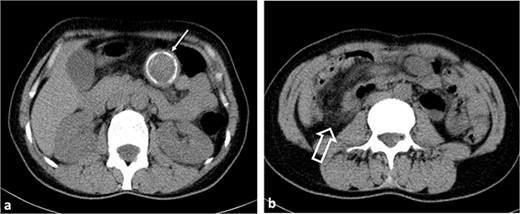

After reviewing the abdominal CT with contrast, the radiologist has reached the conclusion that there is a suspicion of a ‘mesenteric formation’ (Fig. 1).

Axial non-contrast CT images. (a) A hypodense lesion (thin arrow) with peripheral calcification is observed in the left upper quadrant of the abdomen. (b) Ileocolic intussusception is observed in the right lower quadrant of the abdomen (thick arrow).